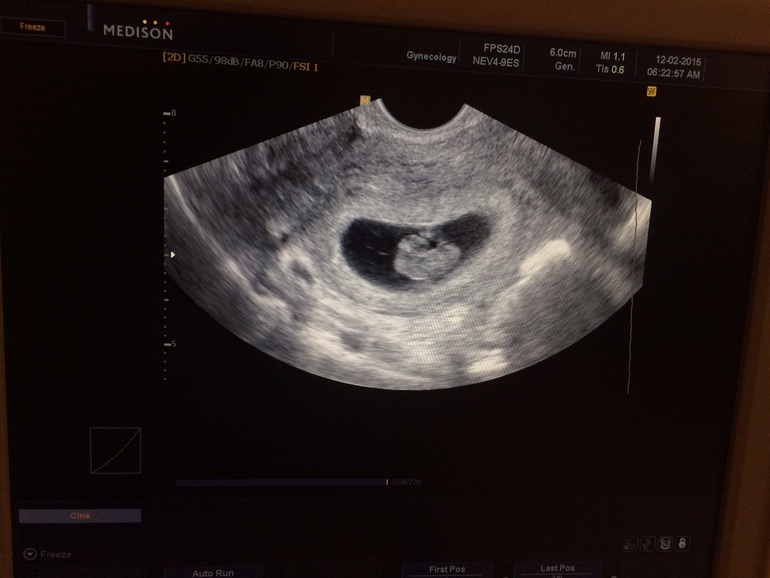

сегодня была на узи!срок 6 нед.и 2 дня нас увидели и услышали!!!!!сердцебиение 140 ударов в минуту!!!я счастлива!!!!чего и вам желаю!!!!!

на 26 дпо было уже и пя и сердце

На 34 дпо в 6+4 слушали сердечко мелкого

В 6 и 4 уже стучало сердечко)